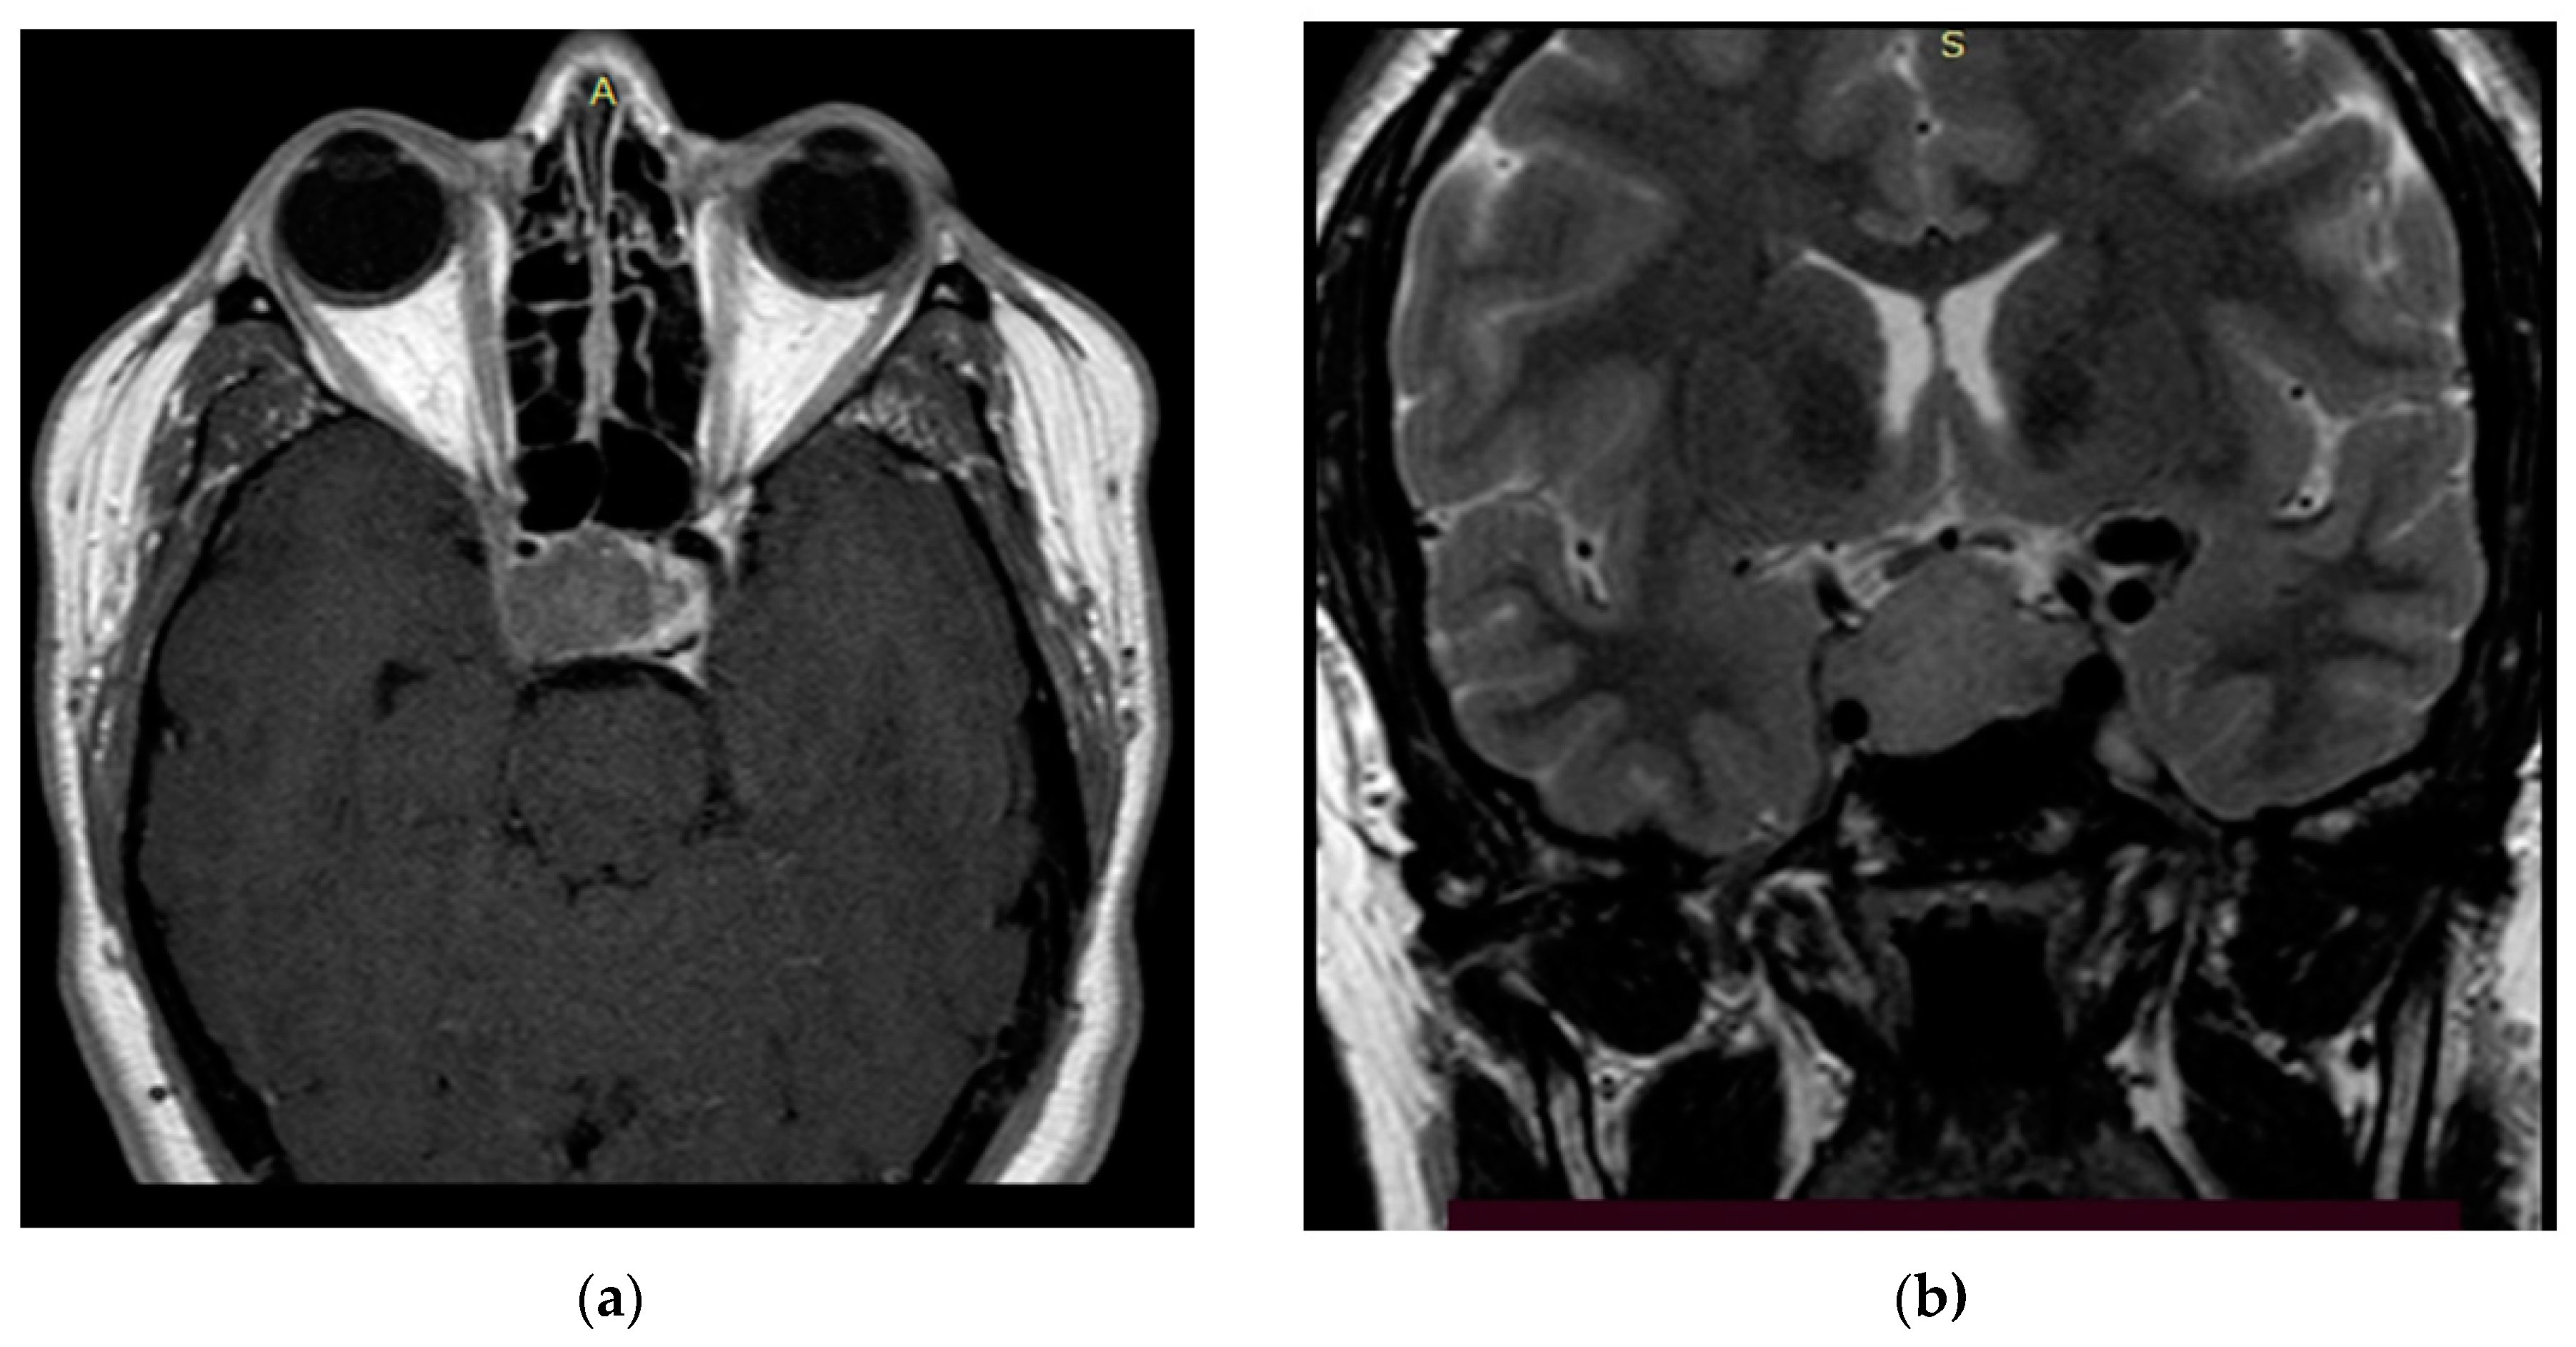

2.3. Clinical Part

The study’s clinical part involved 3 patients. Patients 1 and 2 were diagnosed with hormonally inactive pituitary macroadenomas, and patient 3 with a hormonally active one. All patients underwent endoscopic transnasal removal of the tumor at A.I. Evdokimov Moscow State University of Medicine and Dentistry. Two patients (1, 2) included in the study had previously undergone surgery with resection of the tumor at different times and had continued tumor growth. After the initial intervention, according to the histological examination, patients were diagnosed with PA, while Patient 3 had a primary PA. Additionally, at the preoperative stage, the infiltrative nature of tumor growth into the surrounding tissues was assumed. All patients were admitted to the clinic in satisfactory condition, without focal neurological symptoms. Patients 1 and 2 of the concomitant diseases had hypertension, and Patient 3 had secondary hypothyroidism. Patients 1 and 2, both in the preoperative period and after the surgery, took hormone replacement therapy for hypopituitarism: hydrocortisone and desmopressin. Patient 3 was taking L-thyroxine for a concomitant disease. None of the patients, either in the preoperative period or after the surgery, took chemotherapy drugs, since at the moment they are not included in the standard of treatment for patients with pituitary adenomas, given the benign nature of these types of tumors. All patients underwent a study of the hormonal profile and MRI of the brain with contrast enhancement with an assessment of the tumor spread and its interaction with the main nerve structures (Figure 3, Figure 4 and Figure 5). The patients’ primary characteristics are presented in Table 1.

Figure 3. Preoperative T2 MRI images of Patient 1: (a) sagittal projection, endosuprasellar mass with chiasm compression, and (b) frontal projection, extension to the right cavernous sinus.